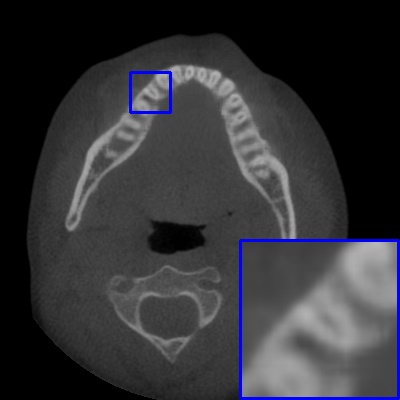

Figure 4: Comparison of MAR images by different methods on real-world MA image. The last image is the metal mask by selecting the pixel area over 2800HU in the MA image.

Results on real-world MAR. We also compare these methods on dental CBCT images with real-world metal artifacts. The visual results on one sample are shown in Fig. 4. We observe that our MARformer-T and MARformer-L well seperate the adjacent teeth and retain their shapes. This shows that our MARformers, though trained on synthetic data, are effective on real-world MAR.